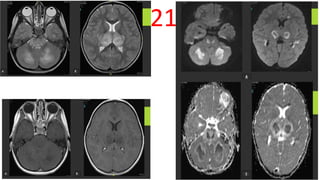

21

Acute Hemorrhagic Leukoencephalitis

• A-Axial T2 WI - showing swelling and bright T2 signal intensity with

attenuated 3rd ventricle and basal cisterns.

• B- Axial CE MRI -no evident post-contrast enhancement.

• C- Axial - DWI ADC -bilateral symmetrical parenchymal areas of bright

sigmal in DWI and low values in ADC maps also seen involving the

corpus callosum and the cerebrellar white matter.

22